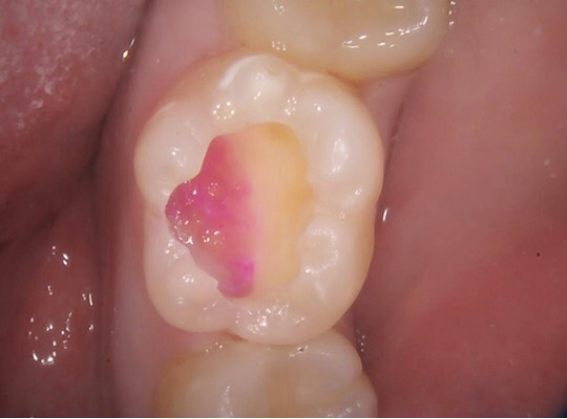

う蝕検知液

「う蝕検知液」を塗布すると、感染した部分が着色しますので、虫歯の取り残しがないうえ、歯を削る量も最小限に抑えることができます。

検知と除去を繰り返し、検知しても染まる部分がなくなるまで治療していきます。そのため時間はかかりますが、虫歯の再発を防ぐためには欠かせません。

そこで、感覚だけに頼らずしっかりと見極めるために当院では「う蝕(虫歯)検知液」の使用を徹底しております。

これにより虫歯に感染している部分は明確に赤く染まり、取り残しなく虫歯の治療を完了することが出来ます。